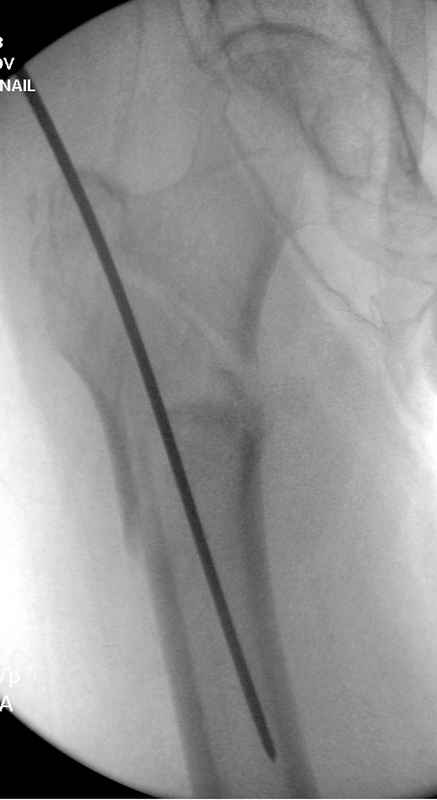

Re: Чрезвертельный перелом бедра

послал Djoldas Kuldjanov 25 Август 2009, 22:19

Здесь 83 года, травма в результате падения